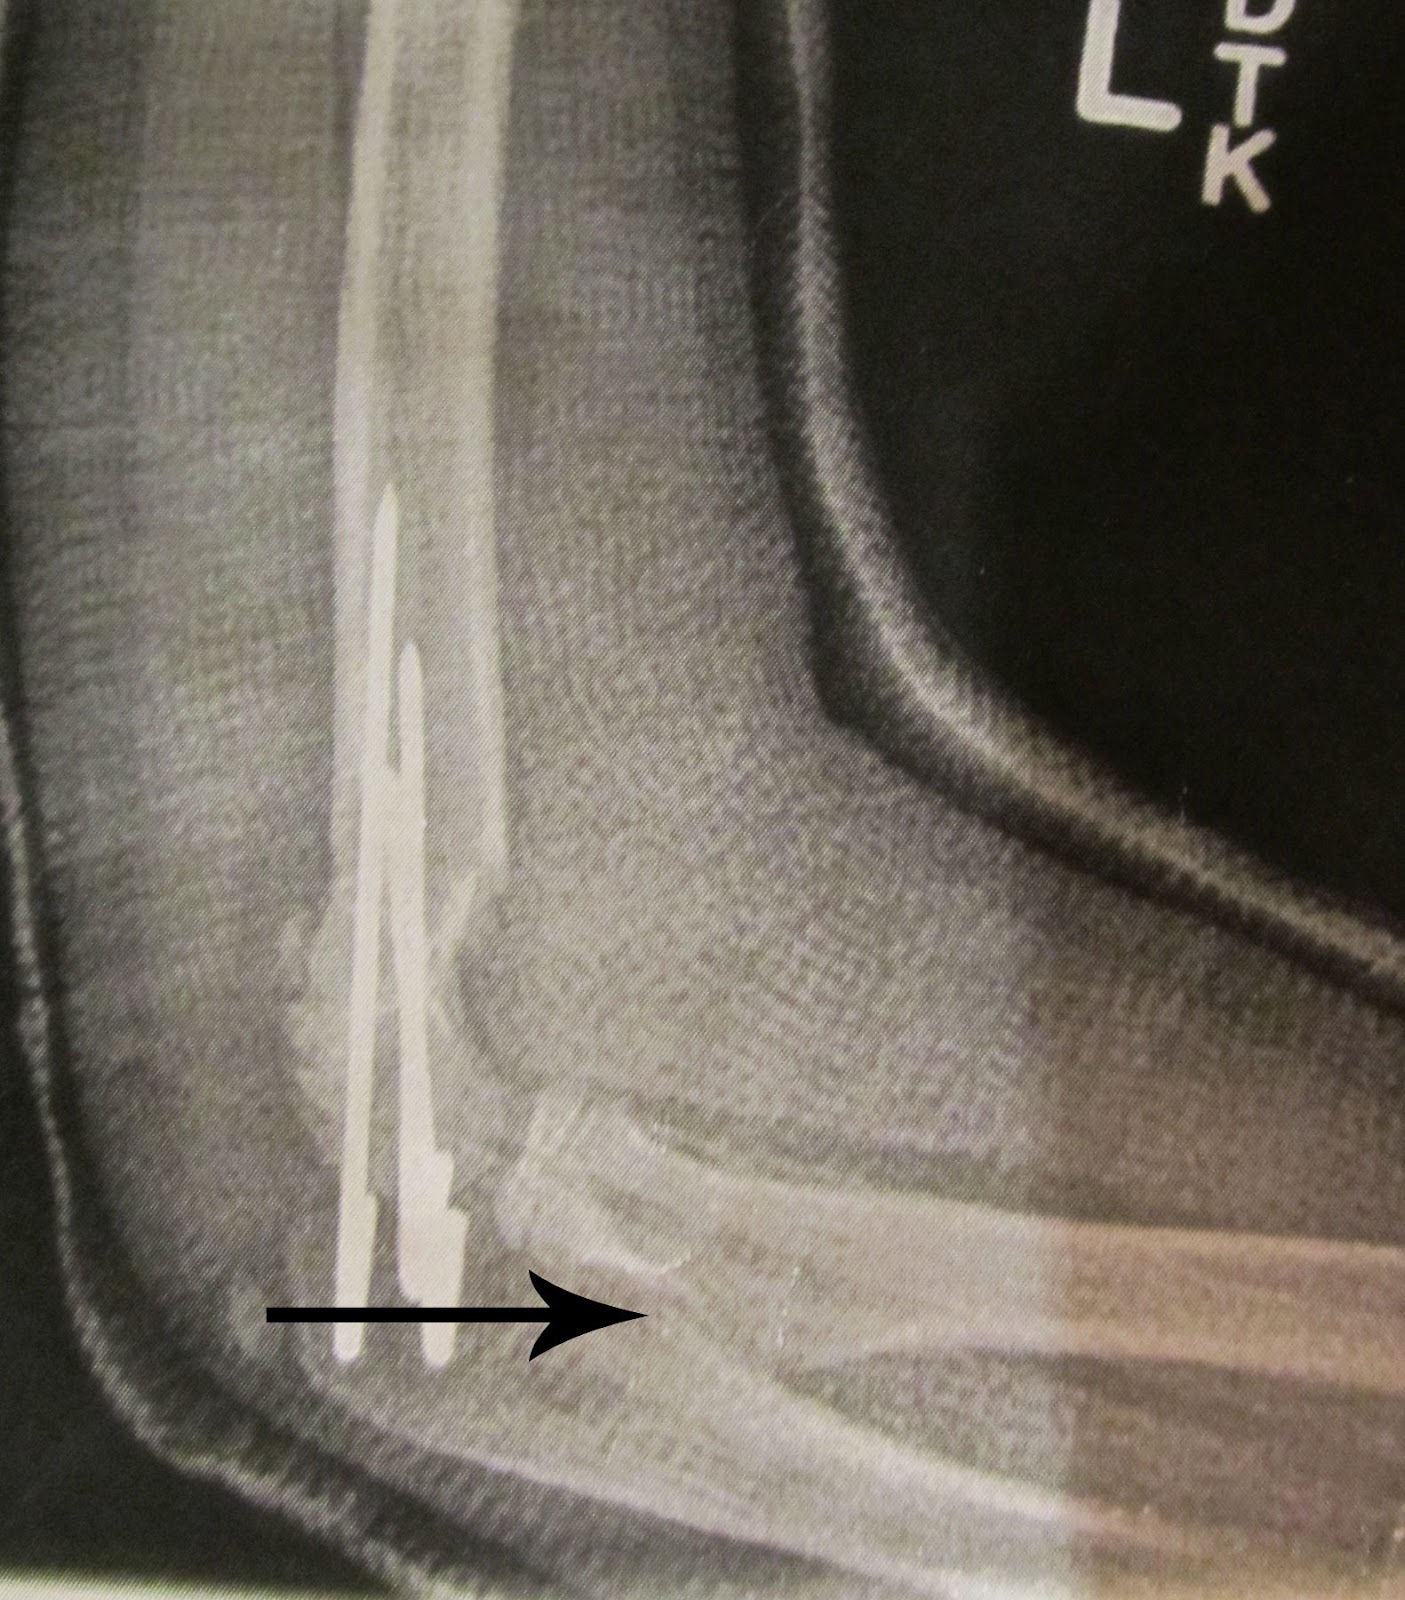

Pins, plates, and broken bones It's been almost a year sin… Flickr

Pins, plates, and broken bones We couldn't resist adding t… Flickr Pins For Broken Bones External fixation is accomplished by placing pins or screws into the bone at various points. Fractures are usually caused by traumas like falls, car accidents or sports. In fractures, the pins are typically. In an external fixator, metal pins or screws are. For bones to heal straight, they may need to be. An external fixator acts as a stabilizing frame. Pins For Broken Bones.

Pins, plates, and broken bones It's been almost a year sin… Flickr Pins For Broken Bones In an external fixator, metal pins or screws are. An external fixator acts as a stabilizing frame to hold the broken bones in proper position. External fixation is accomplished by placing pins or screws into the bone at various points. In fractures, the pins are typically. What is tibia/fibula fracture open reduction and internal fixation? For bones to heal straight,. Pins For Broken Bones.